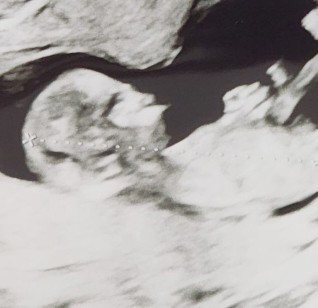

ซาวน์ตอนน้อง 3 เดือนค่ะ เพิ่งมาสังเกตุปากน้องแหลมนี่มันปกติไหมคะแม่ๆ #ขอบคุณล่วงหน้าสำหรับความคิดเห็นค่ะ #ขอคำแนะนำกับแม่ๆด้วยนะคะ #ท้องแรก

แม่ไม่คิดมากนะคะ บ้านนี้ซาวตอน12วีค ยังมีแต่คนบอกเหมือนนกแพนกวิ้นเลยค่ะ 🤣 น้องยังไม่เป็นรูปร่างชัดเจนเท่าไหร่ แม่รอก่อนนะ

น้องน่าจะดิ้นตอนหมอกดถ่ายพอดีค่ะ จริง ๆ ภาพมันเพี้ยนได้เพราะซาวนด์ผ่านน้ำคร่ำ ภาพซาวนด์มันไม่เหมือนการถ่ายรูปนะคะ

เป็นที่ภาพมุมกล้องเพี้ยนไปเฉยๆค่ะแม่